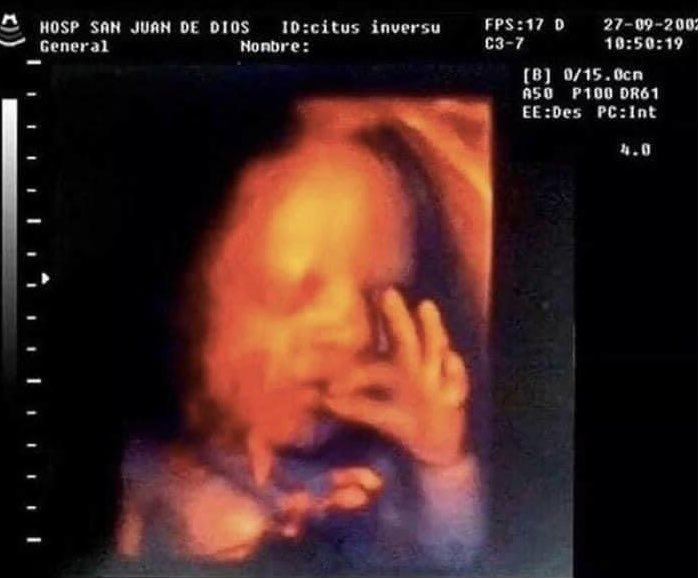

first images of me haha